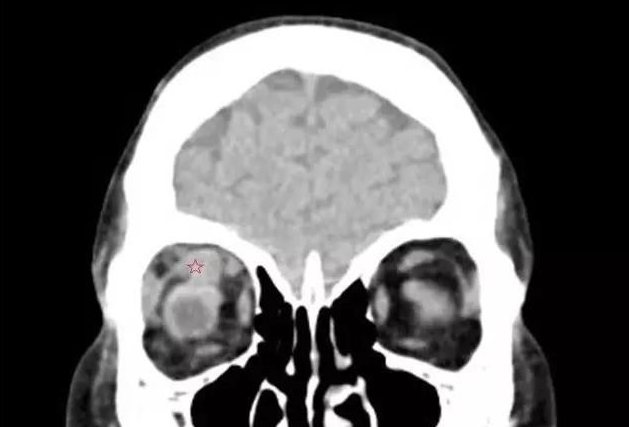

【导读】甲状腺相关眼病,是眼科较常见的疾病之一 。其包括:眼球突出、复视等,对患者的生活和工作带来极大的不便

甲状腺相关眼病,是眼科较常见的疾病之一 。其包括:眼球突出、复视等,对患者的生活和工作带来极大的不便。

来自泉州南安的刘先生发现自己的眼睛莫名的越来越突,还容易流眼泪,转动不灵活,看东西模糊,一个东西变成两个,看马路上的车一辆变成两辆,上下楼梯也踩不准,并且脾气变得暴躁。在当地医生的建议下,今年4月,刘先生又来到了厦门眼科中心斜视与小儿眼科检查,谢仁艺副主任医师在询问了解了刘先生的病情后,并结合各项检查报告判定刘先生是患了甲状腺相关眼病。

谢仁艺副主任医师介绍,刘先生眼睛病变是因甲亢引起,导致双眼眼外肌发炎、肿胀、变性、纤维化, 终失去弹性,这也是他眼球转动不灵活引起斜视、复视的主要原因。